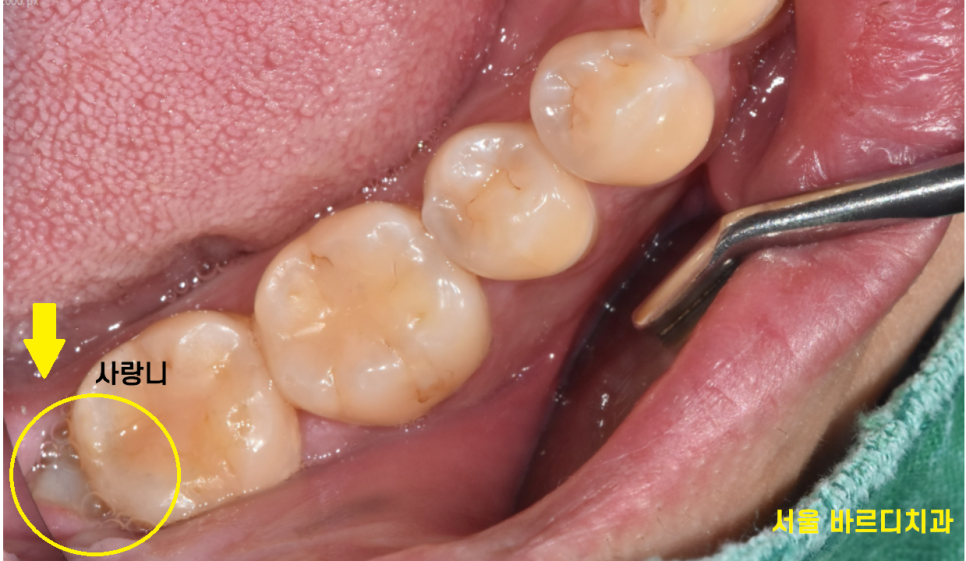

빼꼼~

머리만 살짝 보여줄듯 말듯 하고 있는 상일동 사랑니

이럴 경우 음식물이 자꾸 끼어서

문제가 많습니다.

| 1)냄새도 나고 |

| 2)음식물이 끼어서 충치 유발 |

| 3)사랑니 염증으로 잇몸뼈 녹음 |

사랑니는 없어도 되는 치아라 괜찮지만

내 어금니가 썩을 수 있어서

환자분께 오신김에 뽑고 가시죠~

이건 뽑아야 탈이 없겠어요~